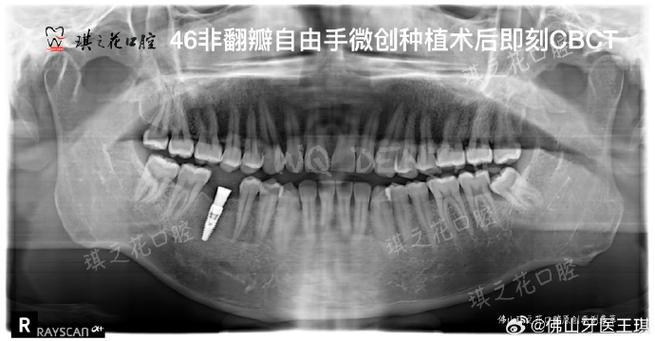

CT在种牙过程中的具体作用主要体现在以下几个方面:一是评估骨量条件,缺牙后牙槽骨会逐渐吸收萎缩,不同患者的骨量差异较大,通过CT可以精确测量缺牙区骨的高度、宽度、密度,判断是否满足种植体的植入要求,如果骨量不足,还可以提前规划植骨手术,确保种植体有稳定的骨结合基础,二是定位重要解剖结构,下颌骨内有下颌神经管,上颌骨内有上颌窦,这些结构周围是神经和血管密集的区域,种植体一旦损伤可能导致下唇麻木、上颌窦炎等问题,CT能清晰显示这些结构的边界和位置,帮助医生设计安全的种植路径和角度,三是指导种植方案设计,基于CT的三维数据,医生可以进行数字化模拟种植,确定种植体的最佳植入位置、角度和长度,选择合适的种植体型号,对于复杂病例,还可以利用CT数据制作3D打印手术导板,术中将导板放置在口腔内,引导种植体精准植入,减少手术创伤,缩短手术时间,四是术后评估,种植手术后,通过CT复查可以观察种植体的位置是否理想,与周围重要结构的关系是否正常,以及骨结合情况,为后续的修复治疗提供依据。

目前种牙前常用的CT检查主要是锥形束CT(CBCT),与传统螺旋CT相比,CBCT具有辐射剂量低、成像速度快、分辨率高、成本较低等优势,更适合口腔科检查,不同类型的CBCT在成像范围和精度上略有差异,医生会根据患者的具体情况选择合适的检查方式,单颗牙缺失可能只需拍摄局部区域,而全口种植则需要拍摄全颅颌影像,以下为不同口腔检查影像技术的对比: